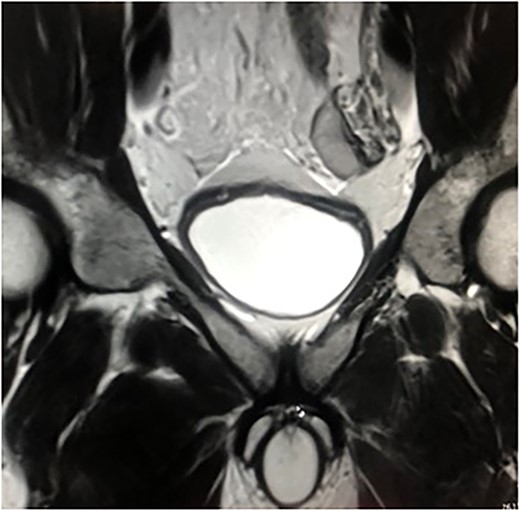

The first case was that of a 28-year-old-man who was admitted to our hospital with left groin pain for 2 months. Physical examination revealed a left groin bulge and an empty left scrotum. Magnetic resonance imaging (MRI) revealed an undescended testis in the abdominal cavity (Fig. 1). The diagnosis was left inguinal hernia associated with cryptorchidism. Sperm count revealed low fertility.

MRI of the case. Left testicle is located in the abdominal cavity.